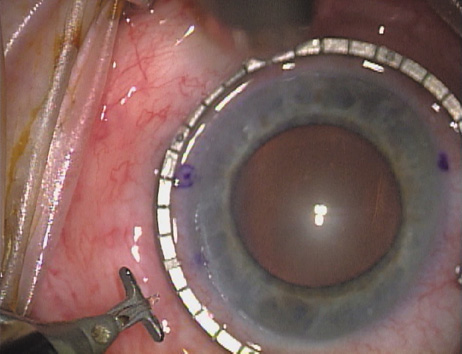

Case 3 is a 48-year-old bilateral hyperope who presented for a refractive surgical consultation. The refraction in his left eye was found to be +3.25 +1.75 × 85. Keratometry was somewhat flat but confirmed WTR cylinder as did corneal topography. Based upon the patient's age, refraction, and somewhat shallow anterior chambers, the decision was made to proceed with a refractive lens exchange. The NAPA nomogram called for LRIs of 55 to 60 degrees with intraoperative pachymetry. Intraoperative keratoscopy confirmed the steep 85-degree meridian (Figs. 2029).

Fig. 20. Keratoscopy, after lifting of the speculum to relieve induced pressure and distortion of the corneal mires, confirms the steep axis of 85 degrees.

Fig. 21. The broad hash marks of the fixation ring are centered just off of the 6:00 limbal orientation mark, over the 85 degree meridian in this left eye. The two cut RK marker is positioned at one extent of the LRI, just under 30 degrees from the central steep meridian and the cornea is marked.

Fig. 22. A second mark is made delineating the opposite extent for a total arc length of just under 60 degrees.

Fig. 23. Following pachymetry measurement over the entire arc length of the incision, an adjustable micrometer diamond knife is set to 90% of the thinnest reading obtained.

Fig. 24. The inferior incision is begun.

Fig. 25. The incision is completed for a total arc length of just under 60 degrees.

Fig. 26. The opposing superior LRI is begun.

Fig. 27. The incision is completed at the corneal mark.

Fig. 28. 6A side-port incision is created for the surgeon's non-dominant right hand, taking care not to intersect the LRI.

Fig. 29. The single-plane RLE incision is completed.